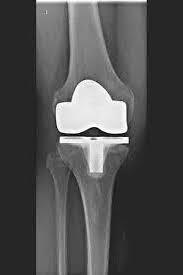

Evaluation and diagnosis: Knee replacement specialists evaluate patients' conditions through a thorough examination, medical history, imaging studies (such as X-rays or MRI scans), and possibly synovial fluid analysis. They determine the extent of joint damage, the appropriateness of surgical intervention, and the best course of action for each patient.

Intraoperative expertise: During the procedure, the knee replacement specialist removes the damaged bone and cartilage and replaces it with an artificial joint made of materials such as metal and plastic, ensuring the correct alignment and fit of the components to restore normal function to the knee.